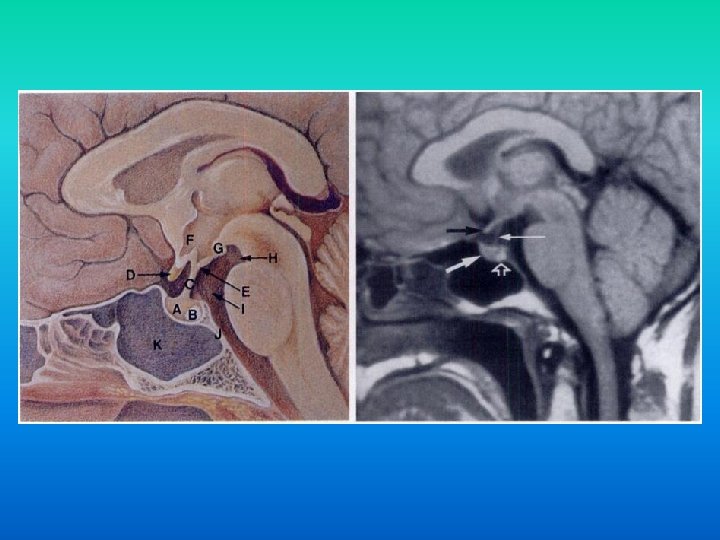

n Patologiile localizate in regiunea sella turcica ocupa un rol aparte in patologiile intracraniene din cauza structurilor de importanta vitala situate in regiune: • Hipofiza. Arterele carotide (si implicit inelul arterial al creerului). Sinusul cavernos (+ nervii cranieni). Chiasma optica (0. 5 cm supraselar). • • •

Microadenomul Hipofizar: In T 1 – hipo. n In T 2 – hiper. n Diagnostic diferential: adenom sau chist Rathke. n

Macroadenomul Hipofizar: Adenom cu diametru >10 mm. n Deseori prezinta arii de necroza si hemoragii. n Initial extind sella turcica, apoi se extind supraselar, compresind chiasma optica sau alte structuri, cu manifestari clinice corespunzatoare. n

Macroadenomul Hipofizar: n Din cauza prezentei diafragmei macroadenoamele au o configuratie tipica de om de zapada. n Diagnostic diferential de meningiom. ♠ Suplimentar numai macroadenoamele extind sella turcica.